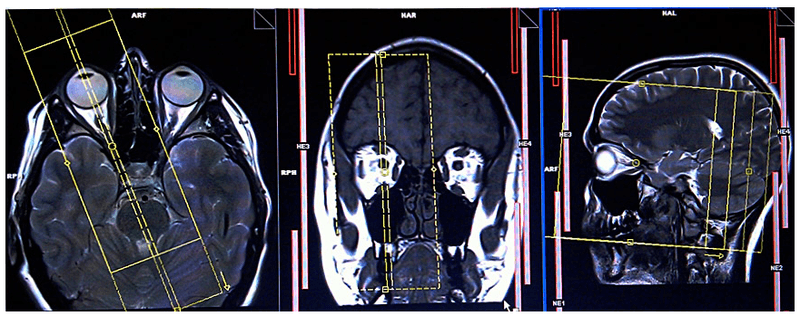

Chụp cộng hưởng từ hốc mắt và thần kinh thị giác có tiêm chất thuốc đối quang từ là kỹ thuật hiện đại, áp dụng rộng rãi trong chẩn đoán bệnh lý của nhãn cầu, bệnh lý của các cơ vận nhãn, các tổn thương trong nón (như bất thường mạch máu, viêm hoặc u dây thần kinh thị...); cũng như các tổn thương ngoài nón (như áp xe, u dây V và tổn thương xương...). Nó có độ phân giải cao để phân biệt các cấu trúc bệnh lý với các cấu trúc bình thường như nhãn cầu, dây thị, các cơ vận nhãn...

- Bệnh nhân nằm ngửa trên bàn chụp, đặt đầu vào coil và giữ cố định, người bệnh có thể được cung cấp một mặt nạ mắt giúp ngăn chuyển động của mắt trong quá trình chụp

- Khi chụp cộng hưởng từ hốc mắt bệnh nhân sẽ được chụp hai thì. Thì ban đầu là chụp cộng hưởng từ sọ não thông thường và chụp khu trú vùng hốc mắt, thì thứ hai là chụp khu trú vùng hốc mắt tiêm thuốc đối quang từ. Thuốc đối quang từ thường dùng là Dotarem, giúp dễ dàng phân biệt sự khác biệt giữa mô bình thường và khối u, nhiễm trùng hoặc các bất thường khác.